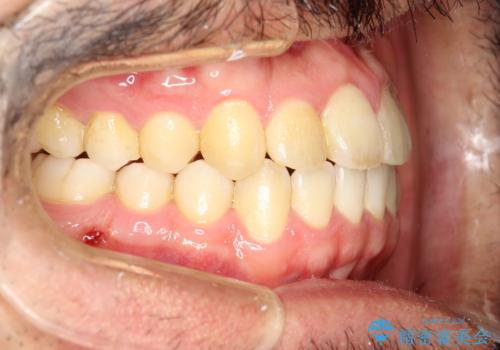

前歯が反対にかんでいる インビザラインとワイヤーを組み合わせた矯正治療

- 前歯が正常とは反対にかんでいるとのことで、来院されました。

患者様がマウスピースを希望されていましたが、上の前歯のがたつきを先にワイヤーで改善する方が早く治療が終了することが可能であるとお伝えし、上顎のみ半年間ワイヤーで治療を行いました。

マウスピースのみでの治療も可能でしたが、治療期間がもう少し延長していた可能性があります。

器具や治療方法についても、矯正治療の前にしっかり相談させていただきます。